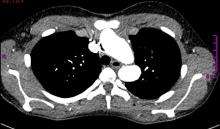

[3]Figure 1. Cross-sectional CT angiogram view of the thorax, where a dilated aortic arch near the origin of the supraaortic vessels is observed in close proximity to the sternum.

A 14-year-old female patient with clinical features of Loeys-Dietz syndrome presented to the authors’ institution with new onset atypical chest pain. The patient related a prior surgical correction of an ascending aorta aneurysm at 18 months of age, in addition to a sibling who had an ascending aorta aneurysm surgically corrected in early childhood. Transthoracic echocardiography showed a tricuspid aortic valve with mild insufficiency, dilation of the aortic root, and dilation at proximal and distal anastomosis of the ascending aorta Dacron tube, without stenosis. Supraaortic vessels showed a tortuous and dilated origin. Given the technical difficulty for surgical correction, computed tomography (CT) angiography of the thoracic aorta was requested with 3D reconstruction for surgery planning. This demonstrated postsurgical inflammatory changes, supraaortic vessels only 2 mm from the sternum, aneurysmal dilatation of the aortic root, ascending aorta, and aortic arch, tortuosity and dilatation of supraaortic vessels, aberrant right subclavian artery, and a normal descending aorta (Figures 1 and 2). A surgical plan was established and was followed throughout the operation by the entire team: